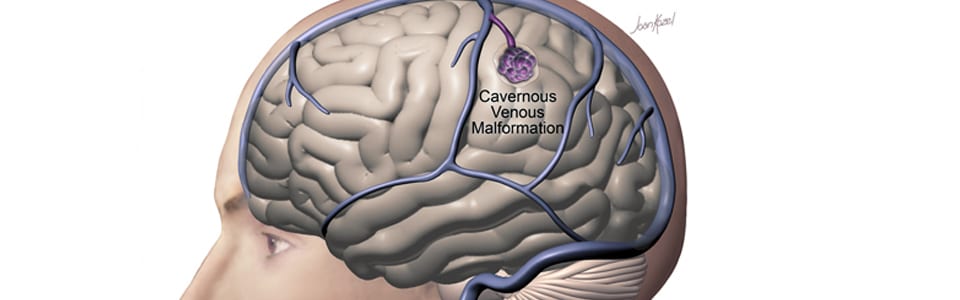

A cavernous malformation (also called a cavernoma or cavernous angioma) is a cluster of abnormally formed, thin-walled blood vessels in the brain or spinal cord. Unlike AVMs, cavernous malformations are low-flow lesions—they do not have the high-pressure arterial blood flow that makes AVMs dangerous. However, they can bleed (usually small hemorrhages), causing headaches, seizures, and neurological deficits depending on their location.

Cavernous malformations are found in approximately 0.5% of the general population. They can occur anywhere in the brain, but those located in the brainstem or deep brain structures pose the greatest challenge due to the critical functions of surrounding tissue.

Notably, cavernous malformations are typically invisible on catheter angiography, which distinguishes them from AVMs and dural fistulas.